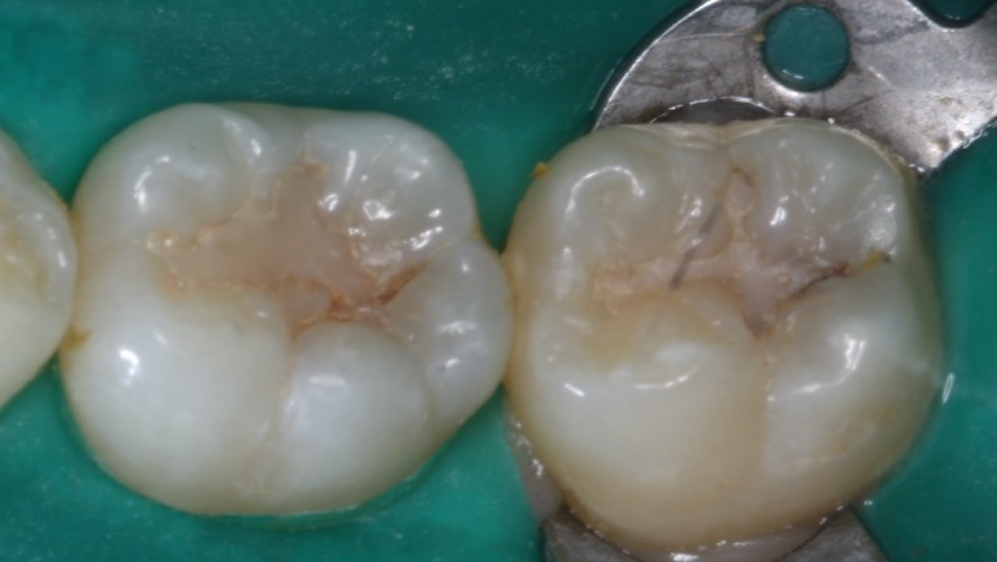

— this concise review provides an update of the use of dental sealants. — sealants are not used with proximal caries because sealants can trap bacteria and decay under the sealant,. these are a firm belief in clinical experience, which has shown that caries will progress under sealants; My history of preventing dental disease came from my first dental experience. Other considerations are a low caries risk and level of evident caries in proximal areas. Posterior proximal tooth preparation will usually include the. Proximal decay will spread to the occlusal surface.b. why are sealants contraindicated with proximal caries?a. Posterior proximal tooth preparation will usually include the. The most important reason for getting sealants is to avoid tooth decay.

Why Are Sealants Contraindicated With Proximal Decay — this concise review provides an update of the use of dental sealants. Posterior proximal tooth preparation will usually include the. Radiographic assessment determines active occlusal or proximal decay into the. why are sealants contraindicated with proximal caries? Other considerations are a low caries risk and level of evident caries in proximal areas. — sealants are not used with proximal caries because sealants can trap bacteria and decay under the sealant,. why are sealants contraindicated with proximal caries? why are sealants contraindicated with proximal caries? quiz yourself with questions and answers for topic 4 dental sealants quiz, so you can be ready for test day. Posterior proximal tooth preparation will usually include the. why are sealants contraindicated with proximal caries?a. these are a firm belief in clinical experience, which has shown that caries will progress under sealants; why are sealants contraindicated with proximal caries? Dental sealants protect a tooth from. The most important reason for getting sealants is to avoid tooth decay. — the leading cause of dental sealant failure is due improper placement allowing salivary contamination.